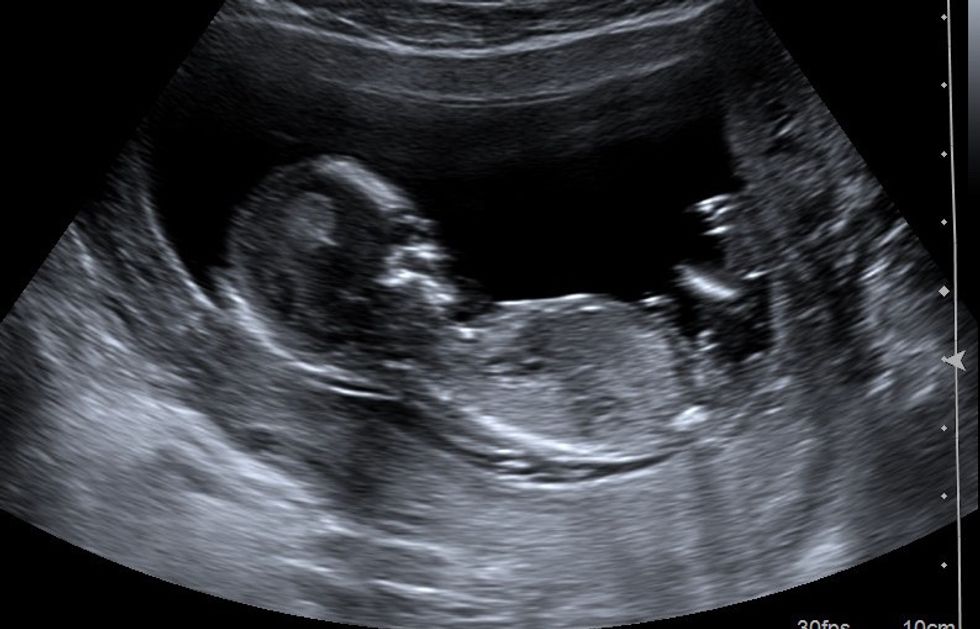

Hulumtimi i ri ka zbuluar diçka shumë interesante se edhe çka tjetër na zbulon ultrazëri për beben ende të palindur.

Hulumtuesit tashmë disa vite besojnë që shenjat e para të majtakëve apo djathtakëve te fëmijët shfaqen derisa janë të vegjël, mirëpo tani konsiderojnë që ultrazëri mund të na zbulojë shumë më herët cila dorë do të jetë dominuese në jetën e fëmijës.

Prandaj, ultrazëri do të mund të na ofrojë dëshminë më të mirë – nga java e 13-të e shtatzënisë, fëmija deri sa është ende në barkun e nënës do të thithë gishtin e madh të dorës së majtë apo të dorës së djathtë.